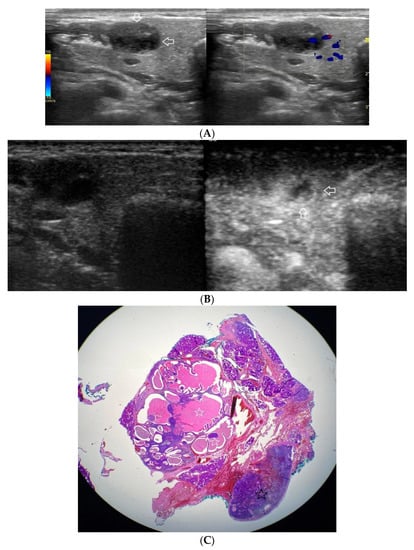

Figure 2.

(A−C) Pleomorphic adenoma. (A) Routine ultrasonographic examination in B presentation and colour Doppler: a well-demarcated focal lesion of a homogeneous echostructure (white arrows). On CD, low blood flow is observed. (B) Contrast-enhanced imaging in arterial phase: a strong homogeneous enhancement of a deeply located part of a lesion (black arrows). A superficial part is not enhanced (white arrows). (C) Pathomorphological image, H & E stain. A large area containing chondroid tissue (black arrows) with glandular tissue located beneath the lesion.

Figure 3.

(A−C) Pleomorphic adenoma. (A) Routine ultrasonographic examination in B presentation and colour Doppler: a small, well-demarcated focal lesion of a homogeneous echostructure. (white arrows). On CD, low blood flow is observed. (B) Contrast-enhanced imaging in arterial phase: a strong homogeneous enhancement of a central part of the lesion. A weakly enhanced peripheral part. (C) Pathomorphological image, immunohistochemistry for CD34. An aggregation of small vessels in central part of the lesion (white arrows).